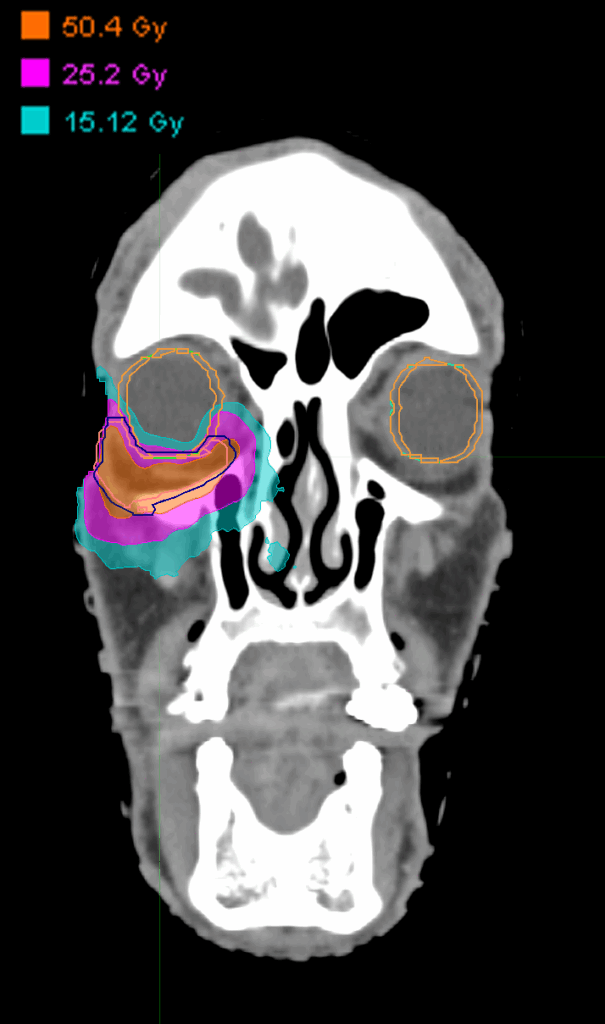

Treatment Plan Images

Treatment Planning Highlights

Fractionation

50.4 Gy in 14 fractions

Dose Distributions

• Prescription to the 72% isodose line

• Max. dose 66 Gy